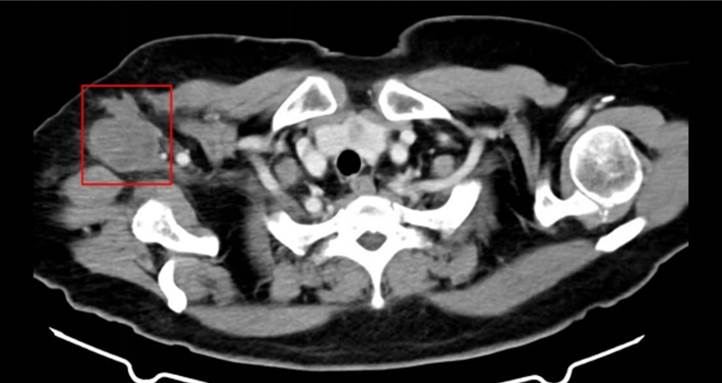

一位68岁女性患者于2024年2月确诊右侧腋窝滑膜肉瘤,辗转省内外多家医院,均被告知无法进行根治性切除。因患者拒绝化疗,去年6月,该患者至南华大学附属南华医院肿瘤科接受调强放疗,治疗后肿瘤一度缩小。然而近期,肿块再次增大,且出现右上肢肿胀、麻木等症状。

面对这一复杂棘手的病情,南华医院医疗团队迎难而上。2025年11月12日,团队成功为患者实施大孔径定位CT引导下的三维后装插植放疗,单次剂量达30Gy(生物等效剂量约120Gy),治疗过程顺利。这一精准放疗新技术的开展,为患者开辟了新的生命通道。

南华大学附属南华医院肿瘤科主任唐三元介绍,插植放疗属于近距离放疗的一种先进形式。治疗过程中,放疗专家首先在CT引导下精准地将“插植针”置入肿瘤病灶;随后,在后装放疗机房内,将插植针连接至后装设备,通过放射源在肿瘤内部直接照射,实现“中心爆破”式杀灭癌细胞。该技术具有高效、精准的特点,同时对周围正常组织损伤极小,安全性高。